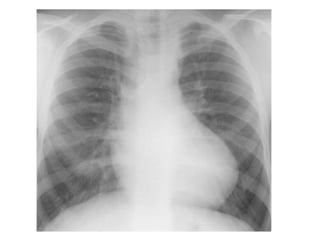

XQUANG TIM PHỔI THẮNG

Cung dƣới trái phồng và kéo dài ra

Phổi mờ hai phổi nhất là vùng rốn phổi

Đƣờng Kerley B

Hình “cánh bƣớm” kinh điển ở hai rốn phổi khi phù phổi